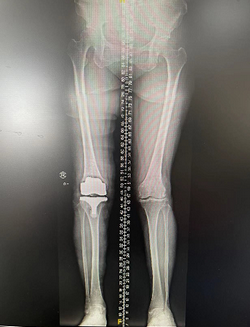

随后,张传开主任、郝亮医生手术团队为其进行了智能导航下右侧人工全膝关节置换术。在智能导航的帮助下,顺利完成截骨及假体安装等操作,使张大婶的下肢力线从术前外翻25°恢复到外翻4°,膝伸直可达0°、膝关节屈曲达至120°,手术很成功。

术后全长片